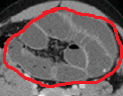

Multiple hepatic metastases — Absolute contraindication for cytoreductive surgery (Courtesy Dr. V. Penopoulos)